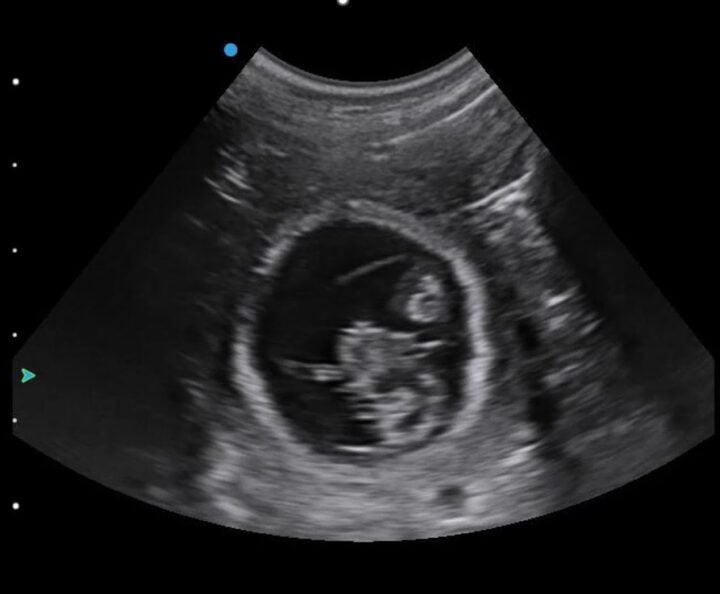

You will likely begin with your depth on its default setting or increased for larger breeds of dog. Once you find a gestation sac (Figure 1), you should optimise your image by reducing your depth and ensuring your focal point is at the level of the foetus. This will allow you to confirm the presence of a heartbeat.